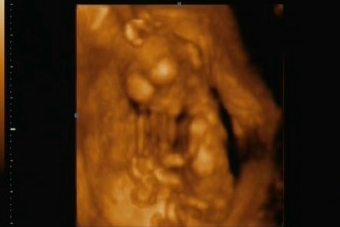

Ígértem tegnap képeket. :)

Hát ők lennének:

Másik:

Kép

A dokira most is három órát vártunk... fél hatra voltunk berendelve... fél kilenckor sorra is kerültünk... (azzal bíztatott, hogy bár igyekszik a szüléshez beérni d elég nehéz így, hogy aránylag messze van egymástól a két kórház és az új munkahelye elsőbbséget élvez, de azért reménykedünk, hogy majd odaér... :( ) sajnos se képet nem tudot adni sem videóra felvenni, de elvittük a fényképezőgépet és azzal örökítettük meg az eseményeket...

Nagyon mókás volt mert elkezdtem nevetni amitől pocaklakónak földrengést okoztam... a látványtól meg nem bírtam abbahagyni a nevetést... kár, hogy a videót nemtudom feltenni...:lol: :lol: :lol: :lol: :lol: :lol: :lol: :lol: :lol:

A nemét még nem látni, de apja szerint tuiti lány mert egyfolytában járt a szája, meg dugdosta a nyelvét! :) :) :) :) :)